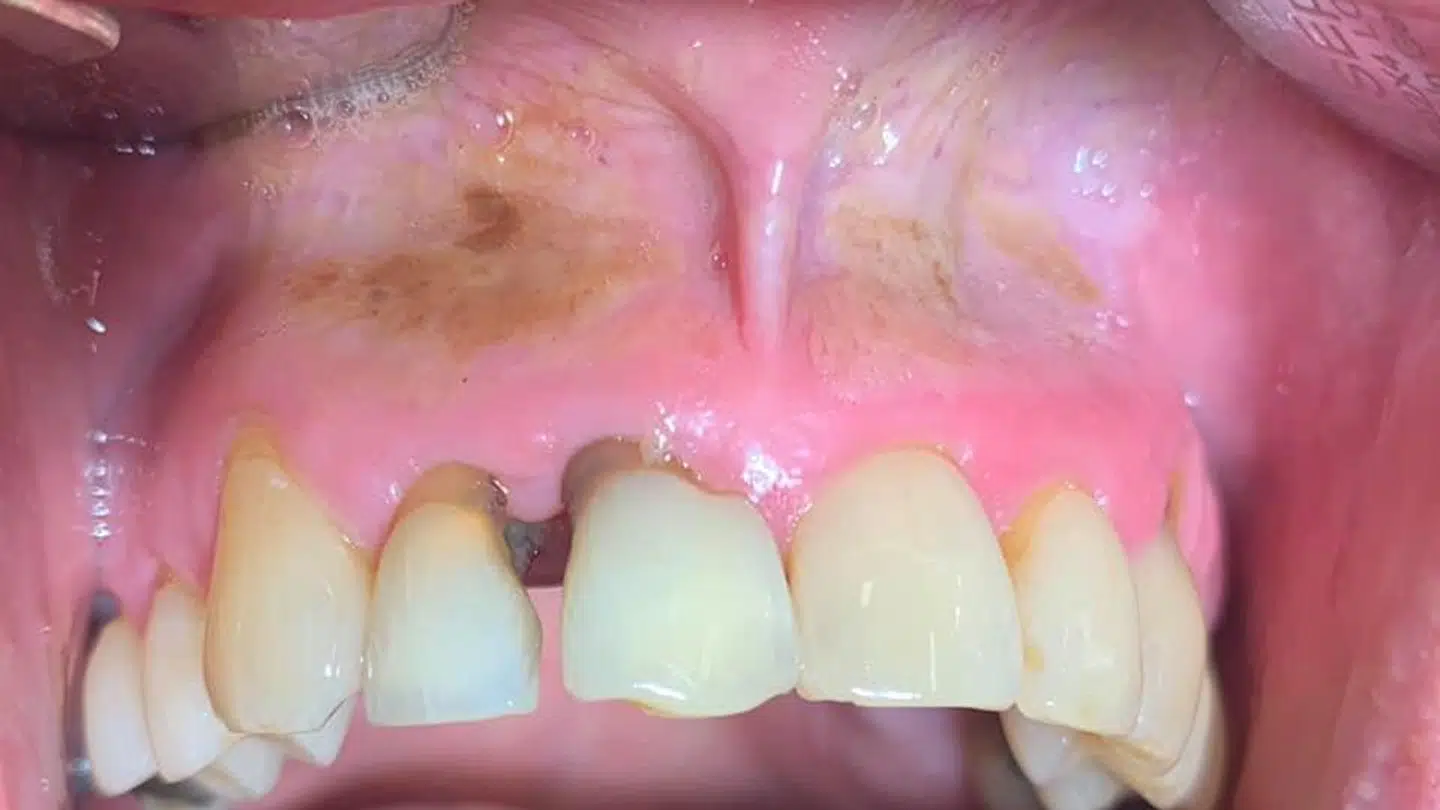

Manden på billedet har brugt snus dagligt i fire-fem år. Han har flere gange prøvet, at der går hul i hans slimhinde, og det medfører en kraftig svien i mund og tandkød.

Rikke Storgaard ser typisk, at de yngre patienter har en tyk hvid slimhinde, der er blevet irriteret, fordi den reagerer på tobakken. Manden selv kaldte billedet for 'chokerende' og 'pisse ulækkert', fortæller hun.

I Tandlægehuset Brande ønsker de at sætte fokus på de alvorlige skader, der følger med brugen af snus. I opslaget vil de gerne vise andre unge, hvordan munden kan se ud efter brugen af snus.

I en kommentar under billedet oplyser de voldsomme sundhedsmæssige konsekvenser. De opfordrer andre til at dele opslaget, så flere kan se det voldsomme billede.